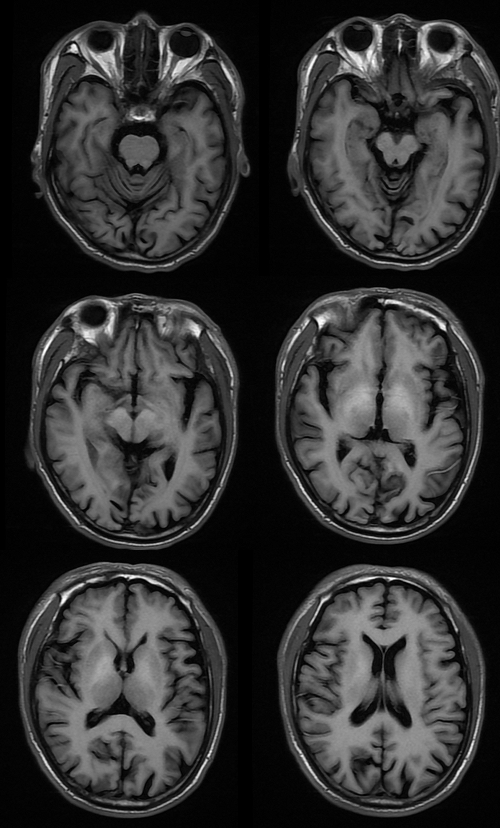

T1

MRI 影像描述:T1W1 可见双侧苍白球对称高信号,T2、T2FLAIR、DWI 相应部位均未见确切异常信号。

普遍接受的 HE 颅脑 MR 常规成像特点为 T1WI 上基底节区尤其是苍白球双侧对称性高信号,其他部位如黑质、中脑被盖以及垂体等也可出现异常高信号;T2WI 上多无明显改变,组织学证实苍白球密度增高是猛沉积的结果。健康人在摄入锰之后可迅速被肝脏清除,并排出人胆道系统。肝硬化病人锰经胆道排泄减慢,导致血锰水平升高及脑中锰聚集增加。因锰离子在第 3 轨道有 5 个不配对电子而具有较大磁矩,能明显缩短 T1 弛豫时间,导致 T1WI 高信号。